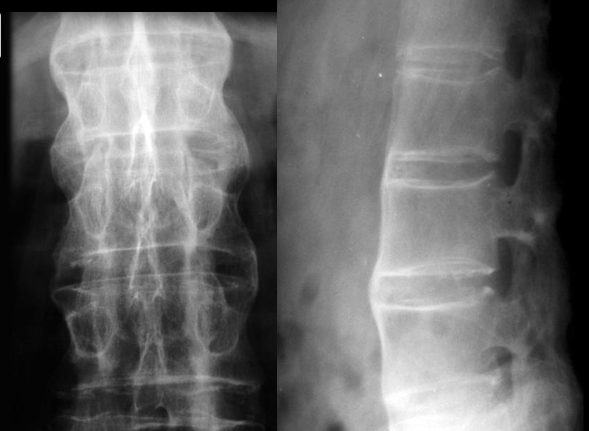

Fratura compressiva da coluna lombar

Causa achatamento do corpo e acunhamento geralmente anterior.

Tipo mais comum de fratura da coluna lombar

Estável.

Mecanismo flexão anterior ou lateral